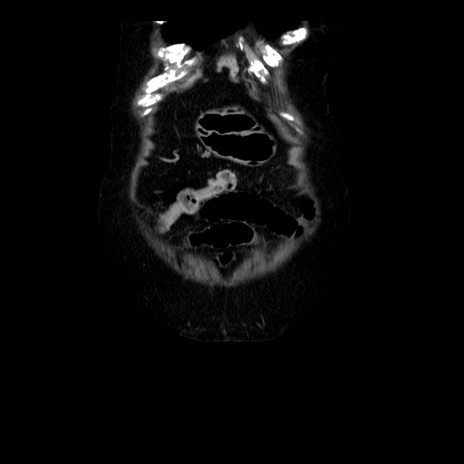

横断像